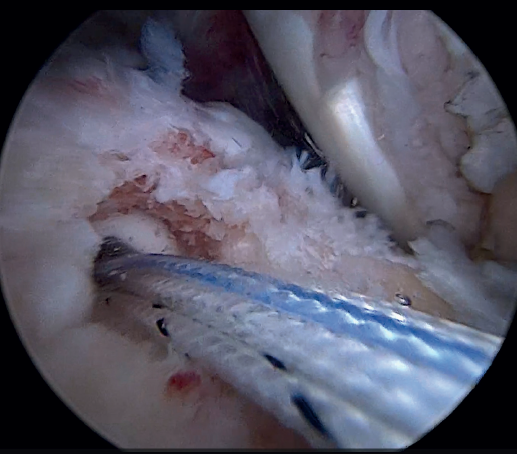

Using penetrating forceps through the anterior portal, the surgeon penetrates the LPB and retrieves one of the suture threads, performing a self-locking Lasso suture in the same step. This is done with two of the three anchoring threads to ensure a correct LPB grip to the footprint of the greater tuberosity and that the tendon does not fray; we do not cut the two threads after knotting (Figures 4, 5 and 6). We also consider it very important to apply the biceps tendon, keeping it as flat and anatomical as possible, avoiding twisting or excessive distension of the tendon. Subsequently, a tenotomy of the LPB distal to these sutures is performed (Figure 7), thus allowing the LPB to function as a superior capsular reconstruction, restricting the ascent of the humeral head.

Tension-free repair of the supraspinatus tendon is then made, using the free thread left at the anchoring and taking advantage of the two sutures passed through and knotted to the proximal LPB fragment (Figures 8, 9 and 10).